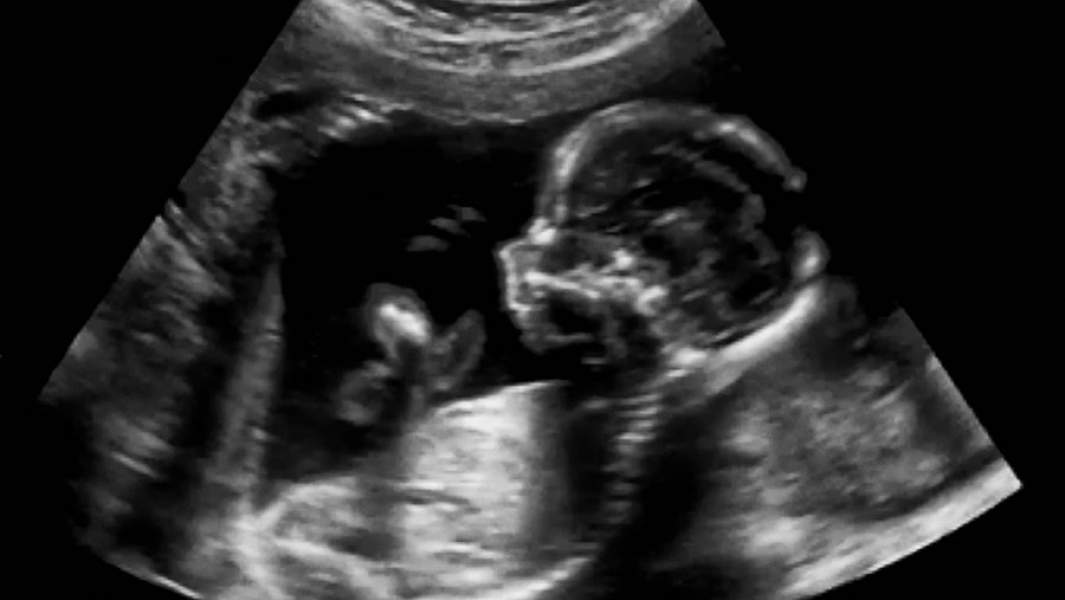

В четверг, 19 апреля, в СМИ стали обсуждать инициативу депутата Заксобрания Ленинградской области Владимира Петрова. Народный избранник предложил наказывать за продажу беременным алкоголя и табака, а также штрафовать самих женщин в положении за потребление этой продукции. Корреспондент iz.ru внимательно изучил подготовленные парламентарием законопроекты, поговорил с автором документов, а также врачами и юристами. Подробности — в материале нашего портала.

Дети матерей, которые так и не отказались от вредных привычек, чаще рождаются с патологиями или дефектами развития. Государство, с точки зрения Петрова, обязано принять меры для охраны жизни и здоровья будущих граждан.

Ведь, по словам специалиста, представительницам прекрасного пола перед приобретением алкоголя или табака придется идти в женскую консультацию, проходить осмотр и УЗИ.

Тем не менее, медик подтвердила, что системное употребление алкоголя и табака теми, кто носит или планирует ребенка, неприемлемо: увеличивается вероятность осложнений во время беременности, повышается риск неправильного развития плода.

Акушер-гинеколог также привела довольно пугающую статистику: у женщин, выкуривающих в день минимум пачку сигарет, частота выкидышей в полтора раза выше, чем у тех, кто избегает табака. А уровень смертности детей при родах у курящих матерей в среднем на 30% выше. Помимо этого женщина, выкуривающая по 20 сигарет в сутки, увеличивает риск рождения ребенка со сниженным на 30% весом.